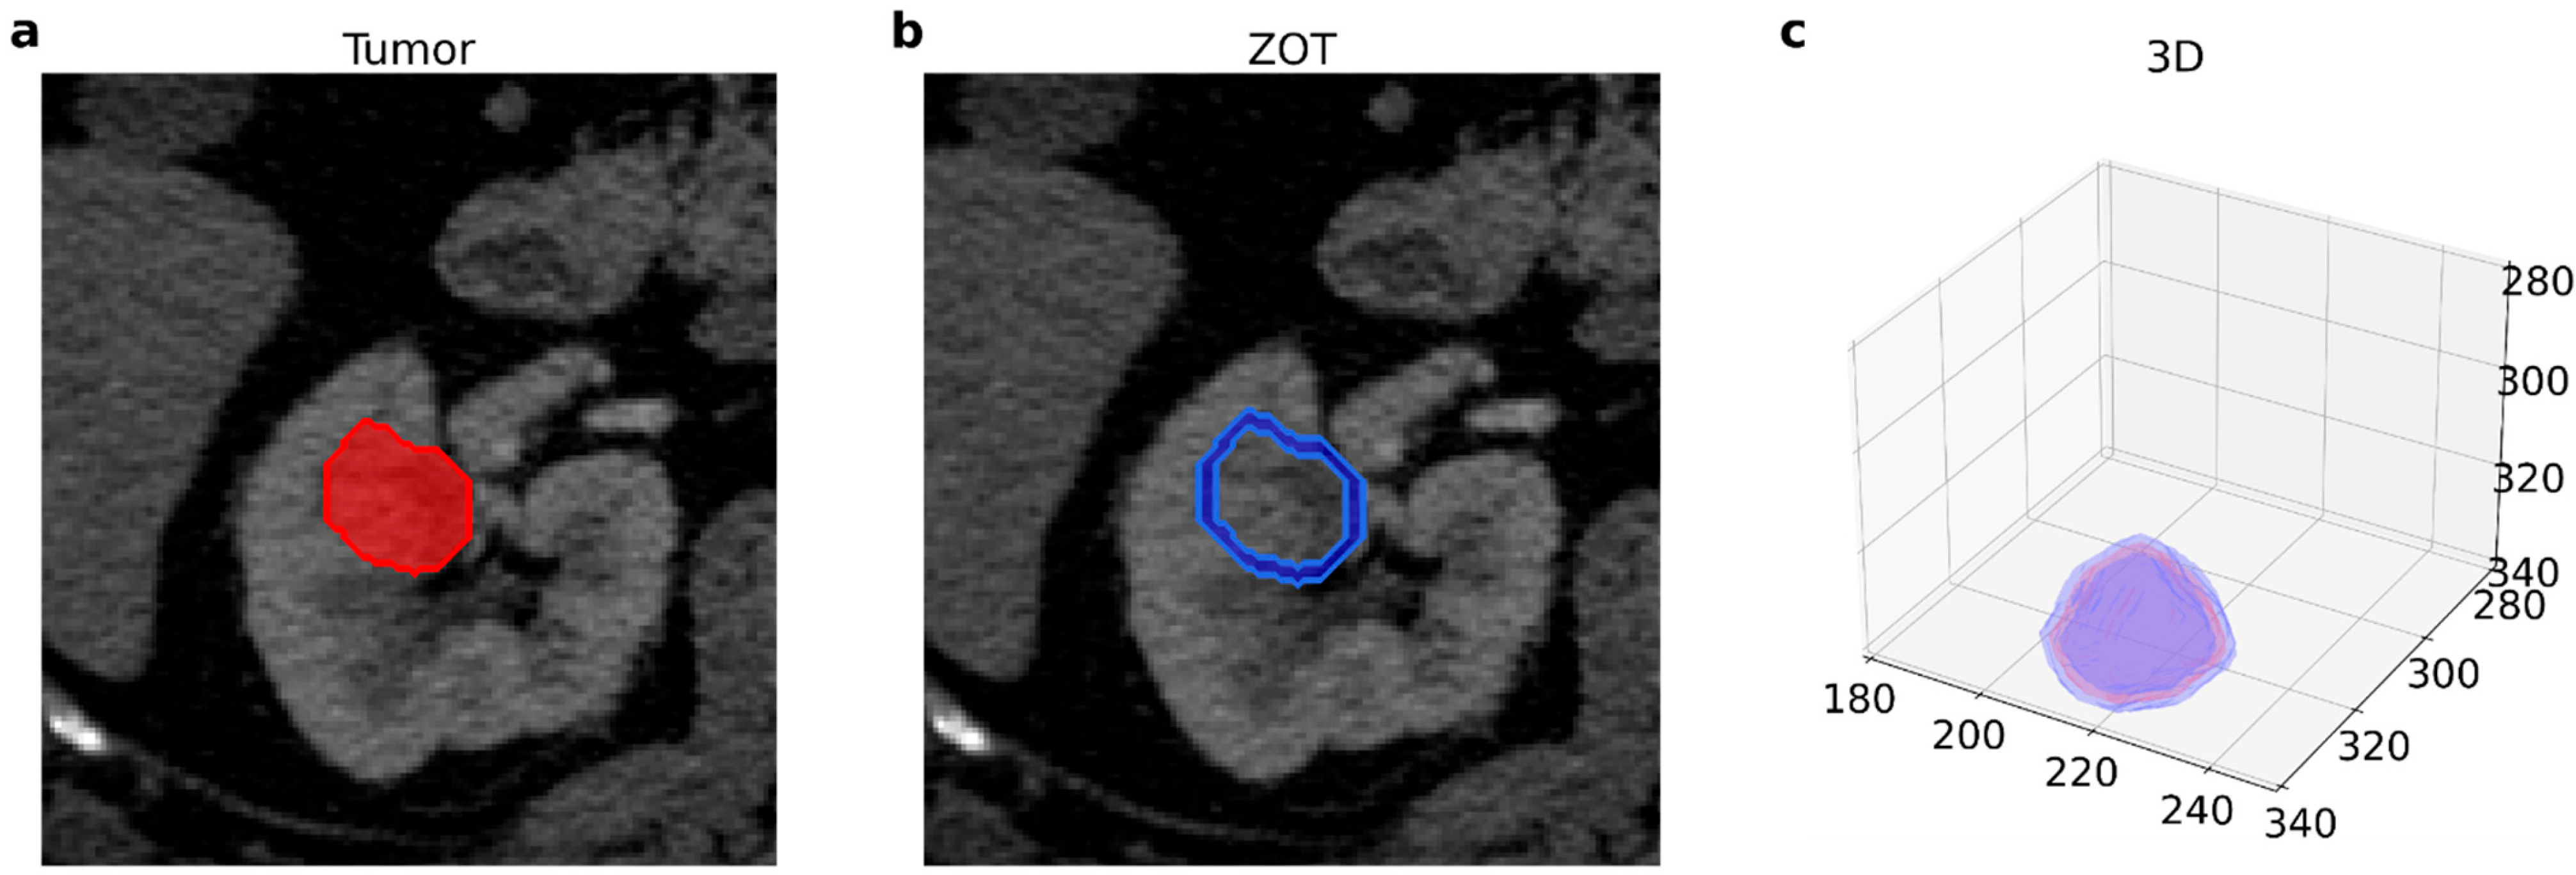

2.2. Image Acquisition and Radiomic Features Extraction

- Renzulli, M.; Mottola, M.; Coppola, F.; Cocozza, M.A.; Malavasi, S.; Cattabriga, A.; Vara, G.; Ravaioli, M.; Cescon, M.; Vasuri, F.; et al. Automatically Extracted Machine Learning Features from Preoperative CT to Early Predict Microvascular Invasion in HCC: The Role of the Zone of Transition (ZOT). Cancers 2022, 14, 1816. [Google Scholar] [CrossRef]

- Zhang, L.; Yankelevitz, D.F.; Henschke, C.I.; Jirapatnakul, A.C.; Reeves, A.P.; Carter, D. Zone of Transition: A Potential Source of Error in Tumor Volume Estimation. Radiology 2010, 256, 633–639. [Google Scholar] [CrossRef] [Green Version]